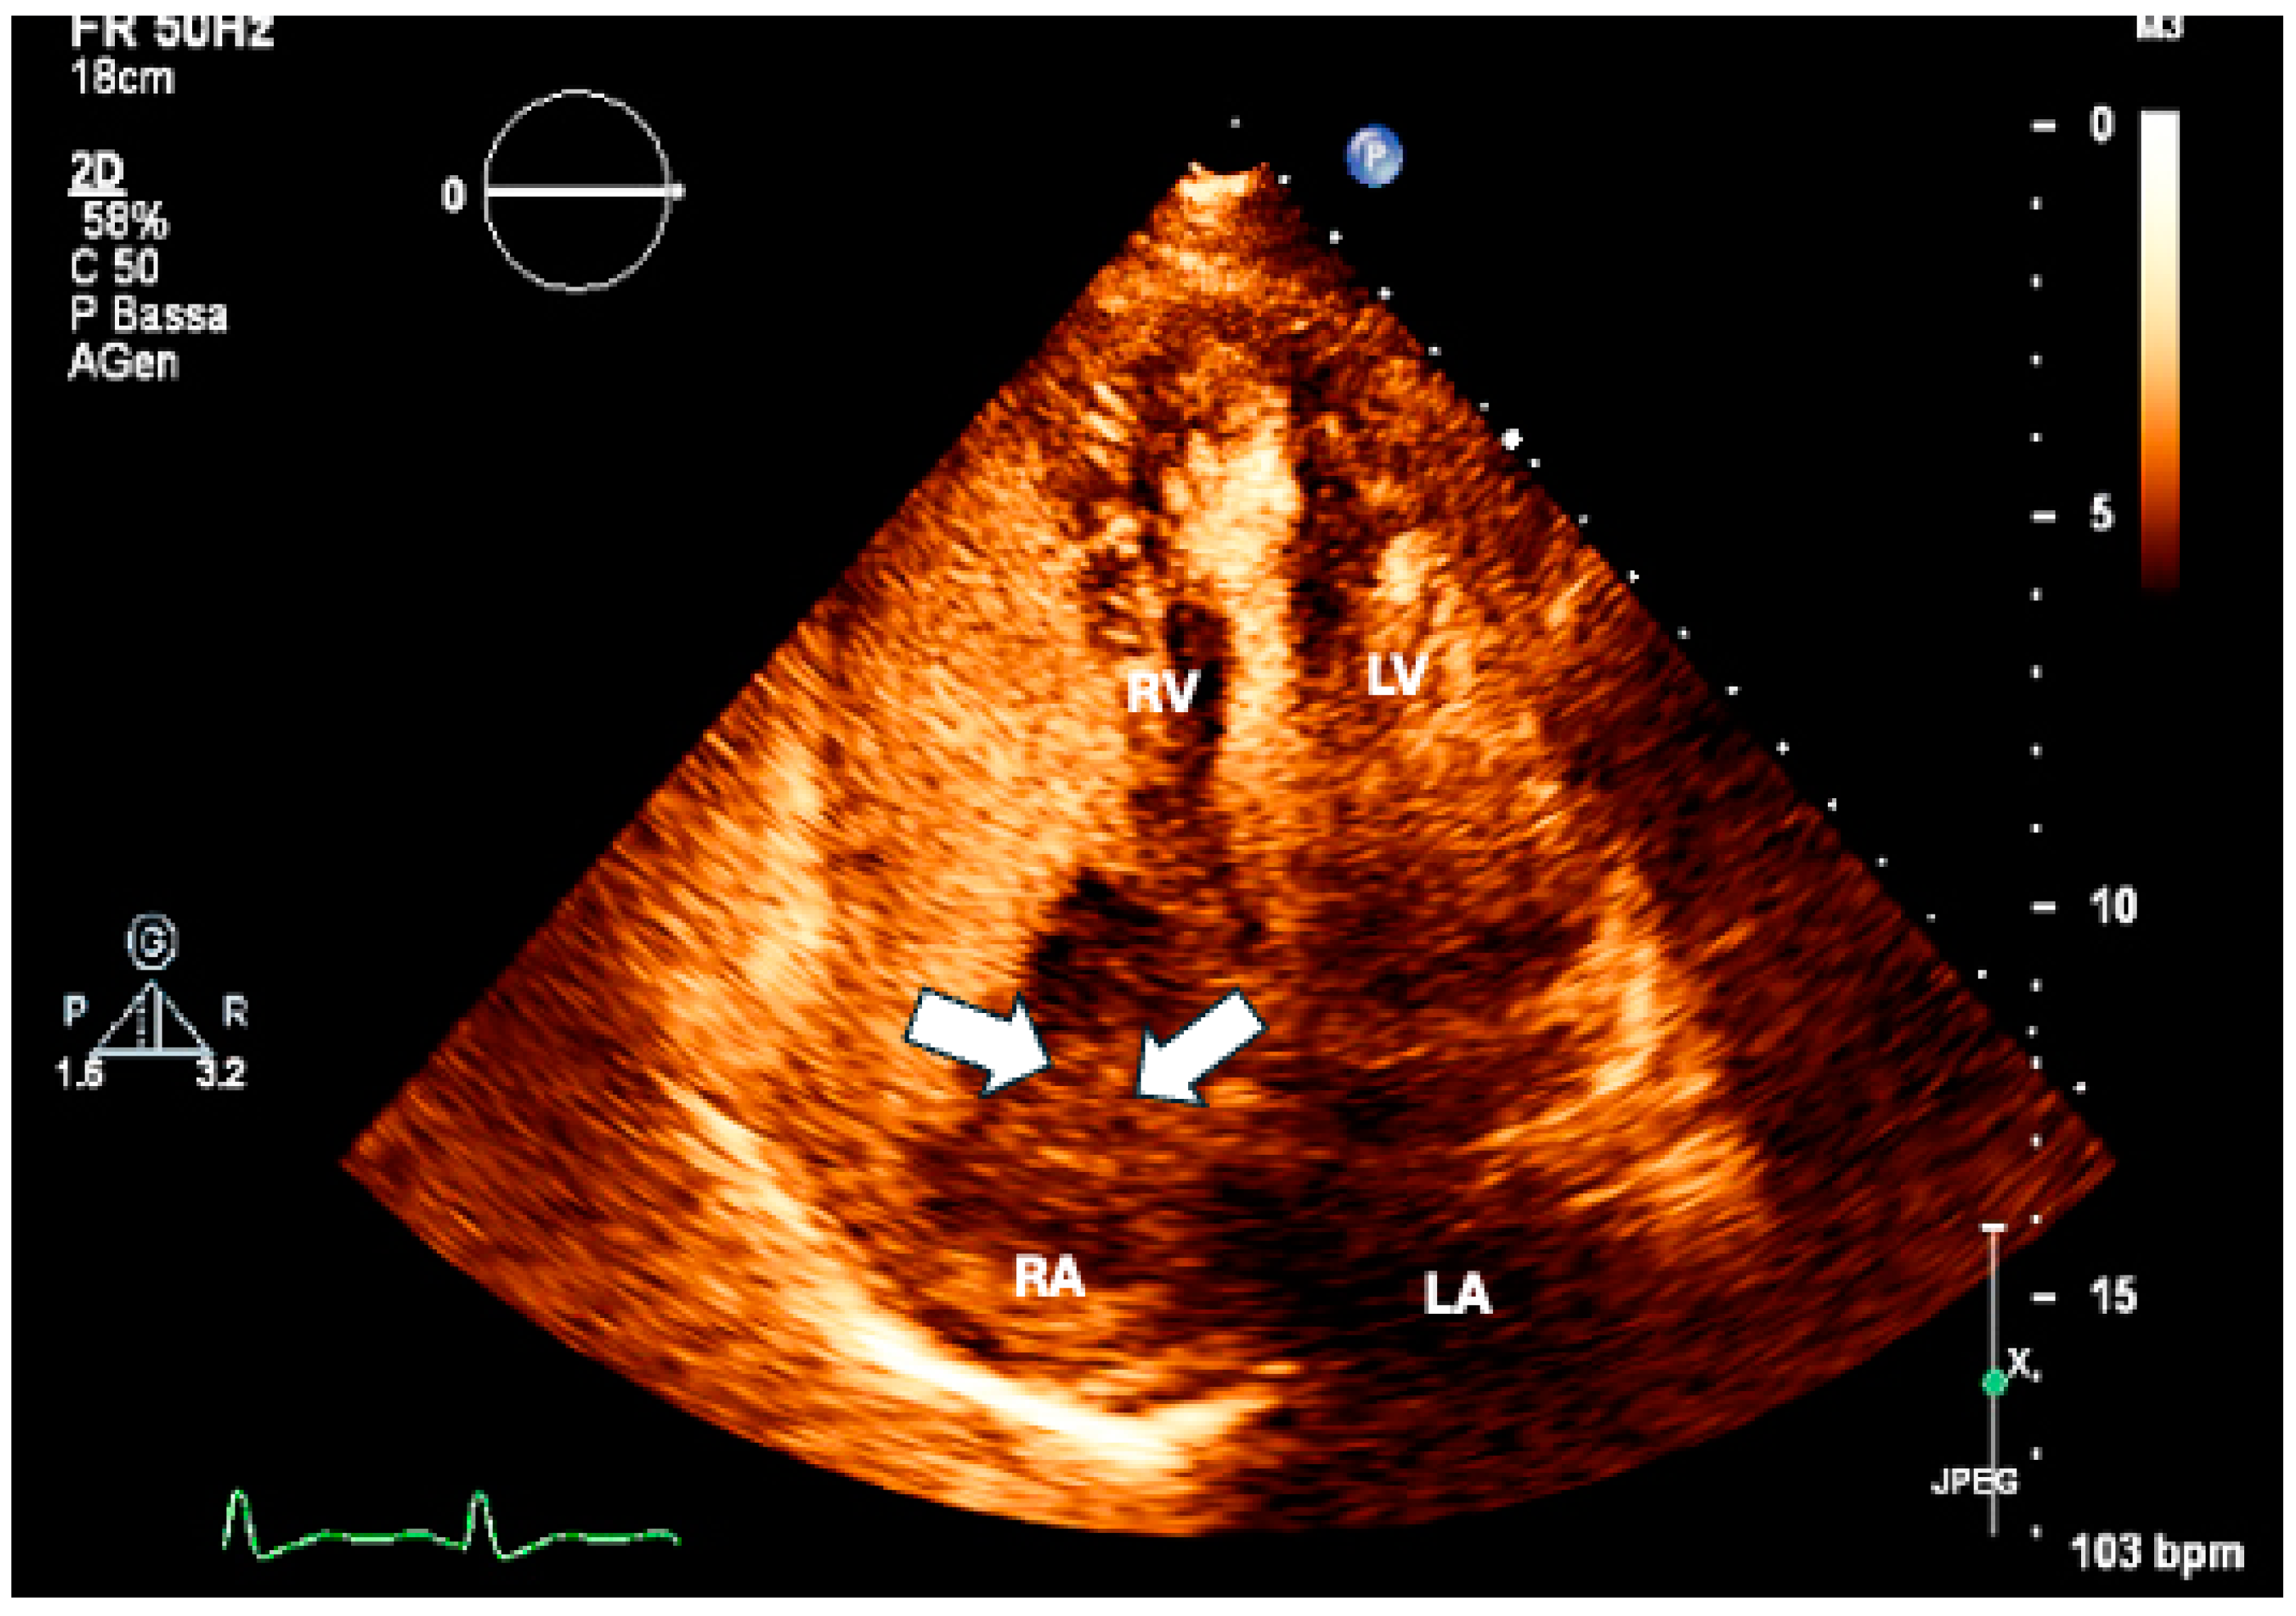

9. Pericardial Involvement

- Mori, S.; Bertamino, M.; Guerisoli, L.; Stratoti, S.; Canale, C.; Spallarossa, P.; Porto, I.; Ameri, P. Pericardial effusion in oncological patients: Current knowledge and principles of management. Cardio-Oncology 2024, 10, 8. (In English) [Google Scholar] [CrossRef] [PubMed]

- Adler, Y.; Charron, P.; Imazio, M.; Badano, L.; Barón-Esquivias, G.; Bogaert, J.; Brucato, A.; Gueret, P.; Klingel, K.; Lionis, C.; et al. 2015 ESC Guidelines for the diagnosis and management of pericardial diseases. Eur. Heart J. 2015, 36, 2921–2964. (In English) [Google Scholar] [CrossRef] [PubMed]

- Khandaker, M.H.; Espinosa, R.E.; Nishimura, R.A.; Sinak, L.J.; Hayes, S.N.; Melduni, R.M.; Oh, J.K. Pericardial Disease: Diagnosis and Management. Mayo Clin. Proc. 2010, 85, 572–593. (In English) [Google Scholar] [CrossRef]